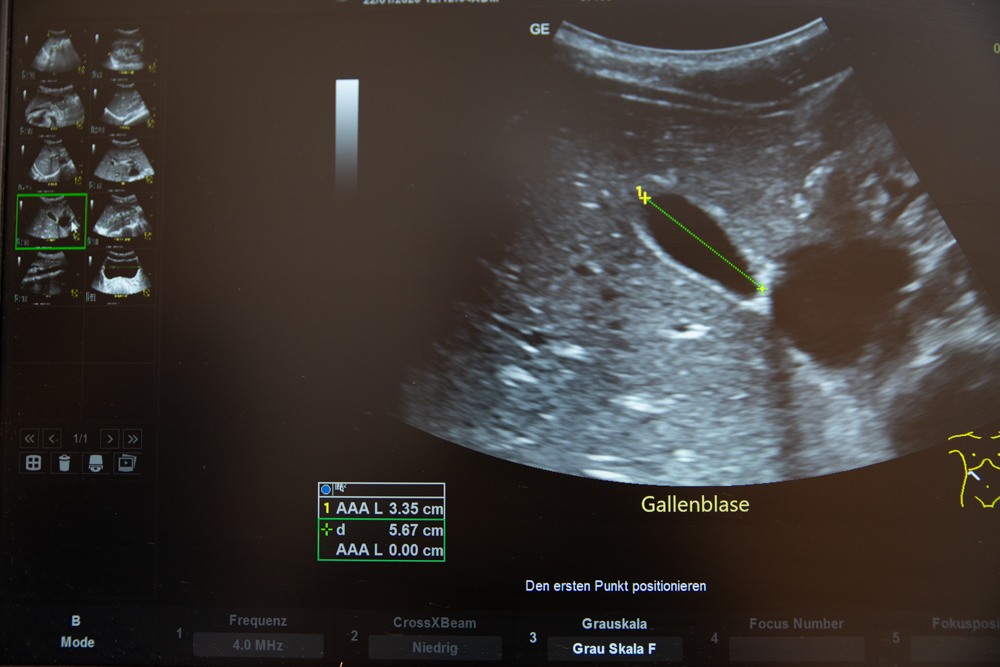

- Sonographie der Bauchorgane

- Sonographie der Urogenitalorgane

- Schilddrüsensonographie

- Gefäßsonographie der Extremitäten